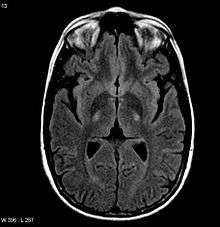

An MRI with increased signal in the posterior part of the internal capsule which can be tracked to the motor cortex consistent with the diagnosis of ALS | |